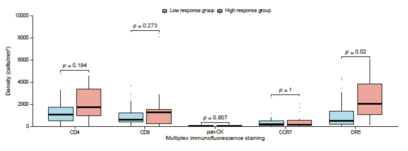

基于Tissue Cytometry技术获得的免疫细胞密度数据,研究开展了关键关联分析,验证了免疫微环境状态对治疗效果的预测价值:

- 区分治疗响应差异:高治疗响应组(肿瘤缩小≥50%)的DR5+细胞密度显著高于低响应组(p=0.02),提示DR5+细胞浸润可能参与增强治疗敏感性。

- 明确预后标志物:高CD8+ T细胞密度与患者更长的生存期(OS,p=0.014)和无进展生存期(PFS,p=0.023)显著相关;高DR5+细胞密度同样与更优OS(p=0.017)和PFS(p=0.028)相关,直接支持“CD8+ T细胞与DR5+细胞是该治疗方案的潜在预后生物标志物”的结论。

- 排除无关因素:CD4+ T细胞、CCR7+细胞、pan-CK+细胞密度与治疗响应或生存无显著关联,通过客观数据排除了非关键免疫群体的干扰。

Figure 12 肿瘤应答情况与免疫细胞浸润的相关性分析(样本量 n=35)。